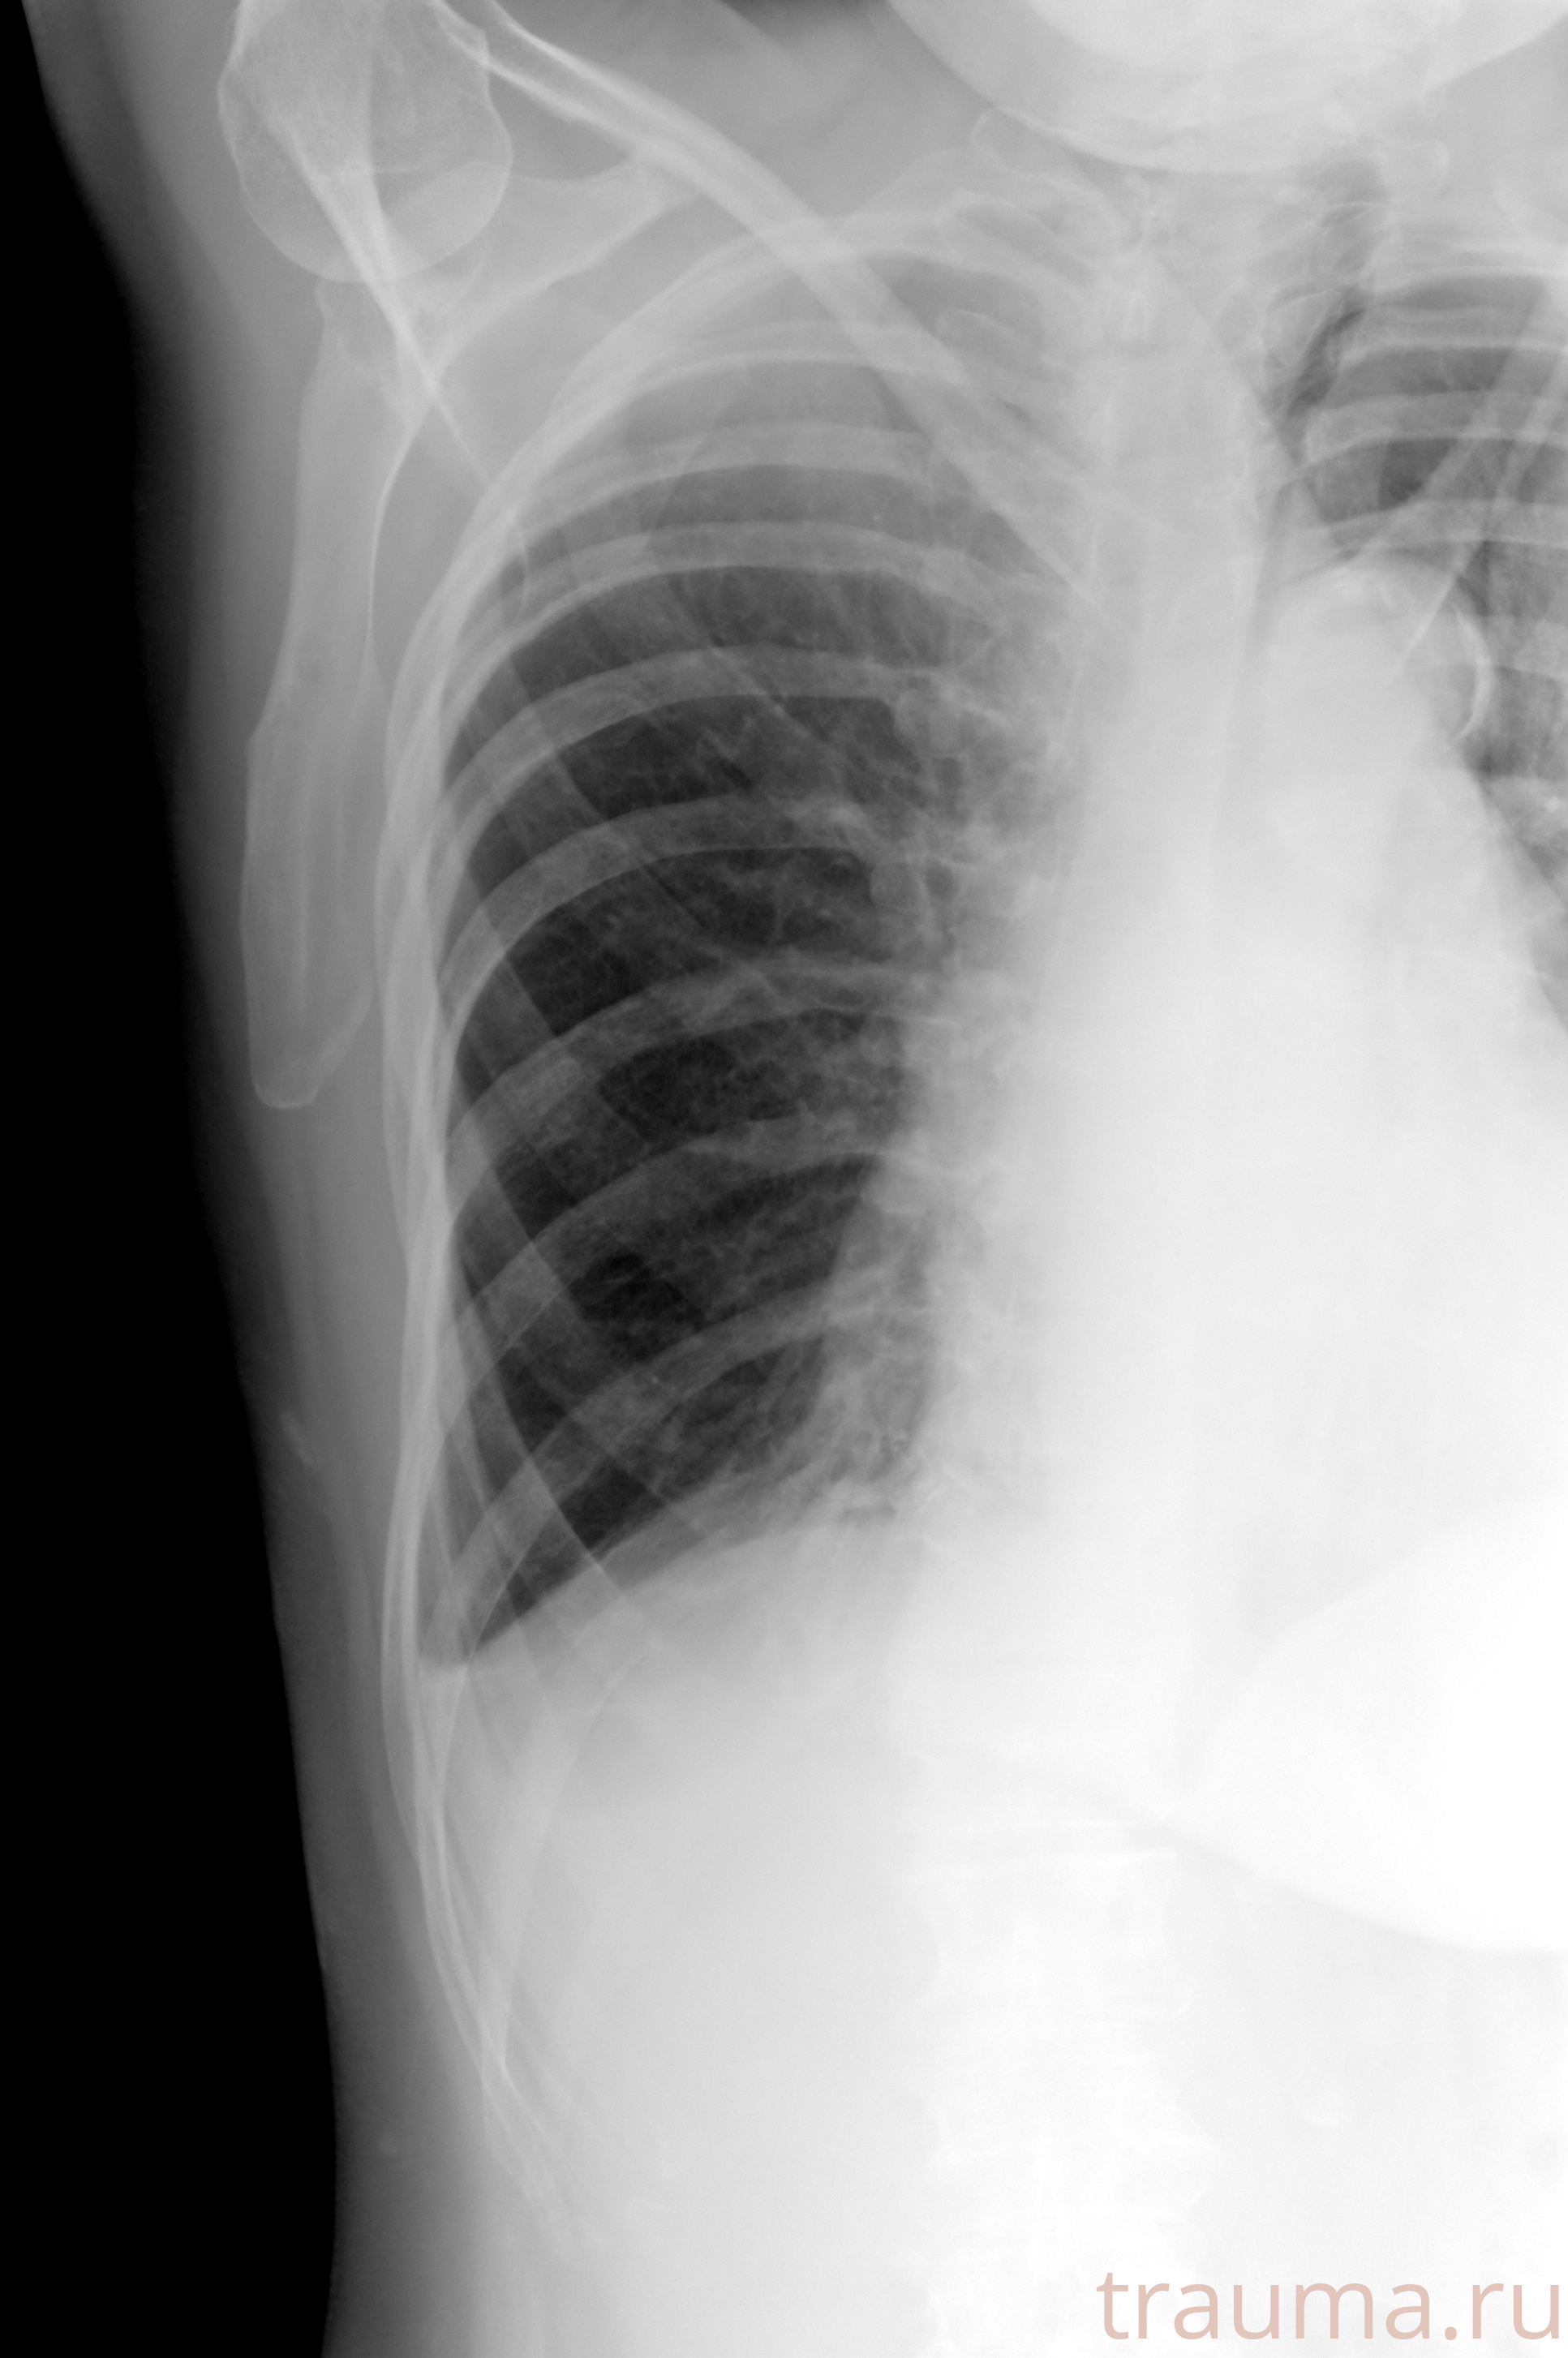

Рентгенограммы

Рентген на дому: по вашему адресу приезжает врач-рентгенолог, травматолог-ортопед с мобильным рентгеновским аппаратом, проводит диагностику травмы или заболевания, делает необходимые рентгенограммы, дает рекомендации по дальнейшему лечению. Получить качественные снимки в домашних условиях возможно благодаря уникальной методике, разработанной МосРентген Центром для института  Склифосовского

Яркость: 1   Контраст: 1   Инвертировать: 0 Увеличение: 1

Перетаскивайте мышь вверх/вниз для контраста, влево/право для яркости. Прокрутка колесом изменяет масштаб. Нажмите Сбросить для возврата к исходному изображению. При увеличении держите мышь в той области, которую хотите рассмотреть.